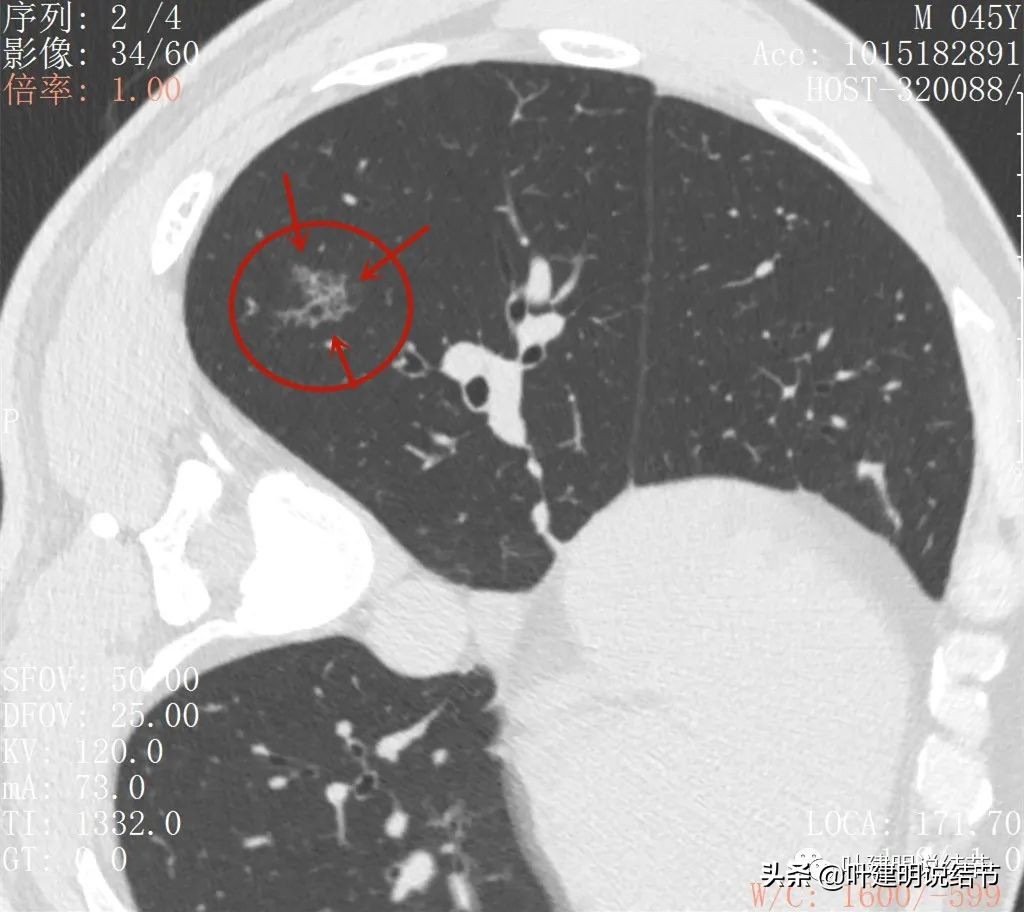

再来看薄层扫描:

病灶感觉很散在,但内部有扩张的细支气管(黄色箭头)、边缘略显不清(绿色箭头),部分有偏实性(粉色箭头)。

边缘血管异常增粗(桔色箭头),边缘显糊(绿色箭头),细支气管扩张(黄色箭头)

病灶似乎非圆形或类圆形,扩张的细支气管壁密度偏高(蓝色箭头),感觉比较僵硬(黄色箭头),病灶轮廓显模糊(黄色箭头)

扩张细支气管壁密度较高,病灶轮廓显糊